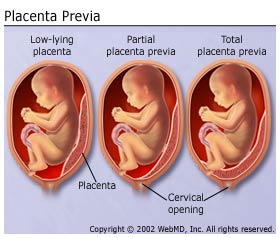

Placenta Previa - Bidan Kita

Placenta Previa - Bidan Kita

Placenta Previa – .

Placenta Previa – .

4 Jenis Plasenta Previa dan Faktor Penyebabnya | Popmama.com

4 Jenis Plasenta Previa dan Faktor Penyebabnya | Popmama.com

Plasenta Previa - Pengertian dan Penyebab

Plasenta Previa - Pengertian dan Penyebab